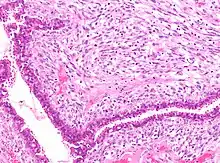

![]() | Tuberculoid leprosy | Skin biopsy showing multiple peri-appendageal granulomas. | Category: Histopathology of leprosy | Leprosy |